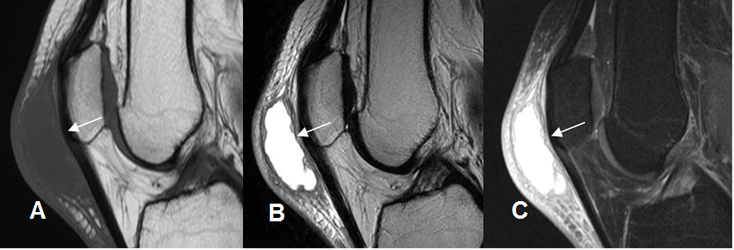

Fig 187 B. Bursitis infrapatelar.

A: RM sagital en T1, B: RM sagital en T2 y C: RM sagital en STIR. Imagen ovalada y de consistencia líquida, en los tejidos blandos de la región infrapatelar, por bursitis. Hay cambios inflamatorios asociados en los tejidos blandos vecinos.